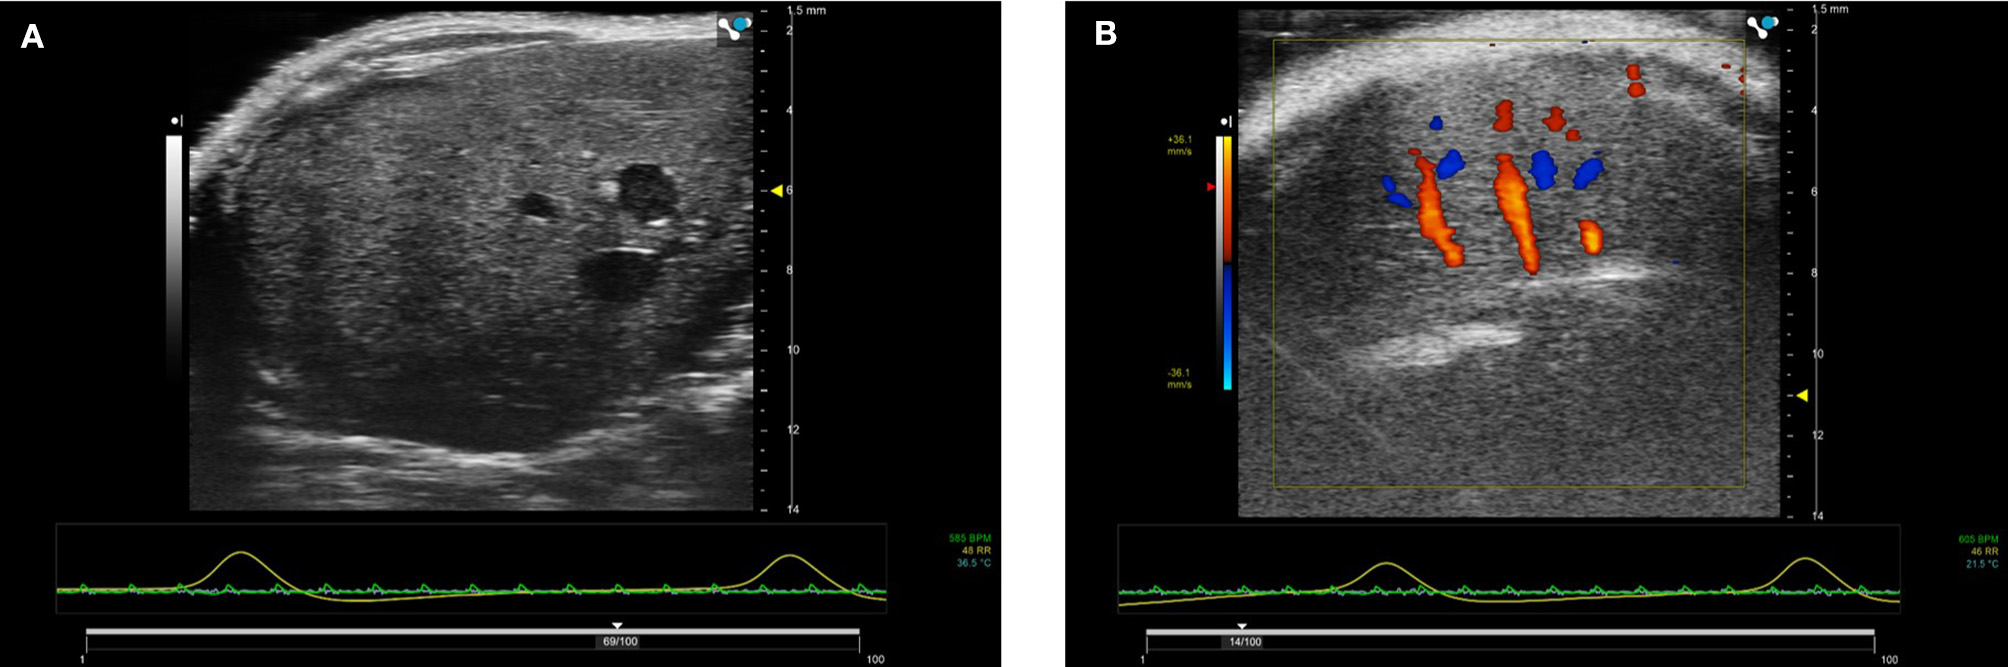

The kidneys in a mouse can either be scanned with the mouse in supine or prone position. The hair can be removed firstly with electric hair clippers and then with depilatory cream. Unless contrast agents are being used, high temporal resolution is not required for imaging the kidneys so multiple focal positions can be selected across the depth of the kidney. Frequencies used tend be between 30 and 40 MHz dependent on the size of the animal. B-mode imaging is used to locate the kidney with the cortex of the kidney tending to have increased backscatter (brighter) compared to the central medulla. Both kidneys can be scanned in the adult rodent. Figure 14 shows an image of a mouse kidney and a duplex image using color Doppler to locate the vessel and direction of flow before placing the spectral Doppler sample volume within the vessel. Renal blood flow can be measured and the renal arterial resistive index calculated (peak systolic velocity—the end diastolic velocity) /peak systolic velocity) and its value indicative of the resistance to blood flow in the vascular bed [19].

FIGURE 14

www.frontiersin.org

Figure 14. (A) B-mode image of kidney. Note the two focal positions on the image. (B) Duplex image of mouse kidney. In the Duplex image, the sample volume is localized using the color Doppler box as an indicator to show where the vessel lies and direction of blood flow.

Vascularity of the kidney can also be studied using ultrasonic contrast agents. When contrast is being used, the mouse is scanned in the prone position avoiding the potential of imaging artifacts caused by intestinal shadowing which can occur when the kidneys are scanned with the mouse in the supine position. Contrast agents are bolus-injected or infused using a syringe pump via the tail-vein. An injection of 50 μl Micromarker (Bracco Research SpA, Geneva, Switzerland) over a 5 second period of a 1:5 dilution is a typical dosing regimen. For acquisition, baseline images are acquired in contrast-specific imaging mode immediately prior to injection of the contrast agent and are saved either as a separate data-set or a temporal stamp is placed on the contrast image sequence indicating when contrast is injected and images taken prior to this time-stamp are considered baseline images. An alternative approach is to inject the contrast agent, then destroy the contrast agent within the 2D plane using a short, low-frequency high pressure acoustic pulse. The low-pressure contrast-specific imaging sequence is then reinstated, with the initial frames immediately after these high pressure pulses regarded as baseline images with subsequent frames displaying contrast enhancement. After contrast injection a long sequence of 2D images are obtained, the length of sequence can be pre-set by the user. Once the sequence has been saved, either in-house software or contrast-specific software developed by the manufacturers can be used to map the intensity of the backscattered signal within the regions-of-interest (eg medulla, cortex) to study the perfusion-dynamics. Metrics of interest include area-under-the curve, time-to-peak enhancement, wash-in rate and these can be used as indicators of blood volume and vessel density [20]. In many instances if an ischemic-reperfusion-injury (IRI) mouse model is being studied, one kidney can act as a control and both B-mode and contrast-enhancement data can then be acquired from both kidneys.